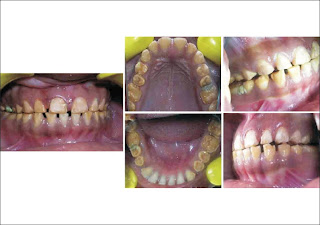

In case B patient had mild grade fluorosis and micro and macro abrasion were employed. Advantage of micro and macro abrasion being its much faster procedure in achieving the desired result compared to other treatment options. However, the main disadvantage is that these procedures employ high speed rotary instrument which can lead to excessive removal of tooth structure is operator does not have the desired skill level. [17]

Abrasion techniques can be successfully employed for discoloration presented either as single line discoloration or patchy type of discoloration, it cannot be successfully employed for discoloration which is more diffuse in nature. [26] Both the bleaching technique and abrasion procedures could be employed only for mild to moderate grade fluorosis. [25],[26] Most of the times, a combined treatment regimen of bleaching and abrasion procedures is employed to produce the desired aesthetic result in patients with yellowish discoloration due to fluorosis. [27]

In case C, the patient had moderate type of fluorosis which necessitated that the patient was treated by veneer procedure. Veneers have been successfully employed for management moderate grade fluorosis, [15] Because of the time constraint given by patient, direct composite veneer treatment option was selected. Advantage of direct composite veneer is that it is done with minimal chair time when compared to indirect ceramic veneers, disadvantage being its long term wear resistance, color stability. [17]